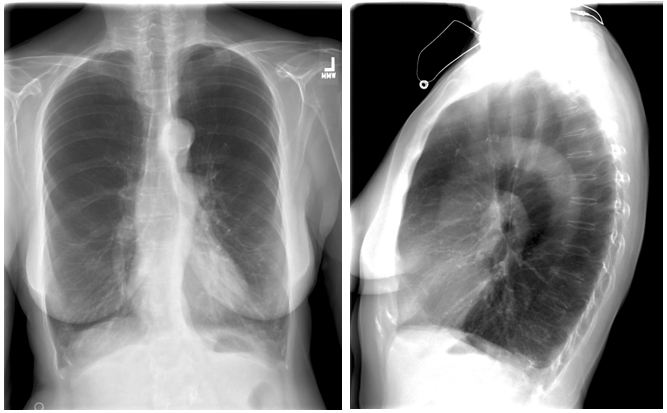

Figure 1.1: Posterior-Anterior and Lateral Chest Radiograph - Demonstrating hyperinflated lungs with emphysema